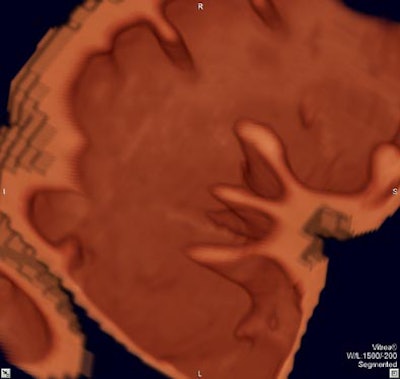

| Virtual colonoscopy images of an asymptomatic 56-year old woman who ingested small aliquots of nonionic iodinated contrast, without dietary restrictions, prior to virtual colonoscopy. The evening before the exam, the patient ingested a half dose of mild cathartic, markedly reduced from standard regimens. Images top to bottom: Sagittal view of cleansed colon following the preparation; corresponding cutaway view; volume-rendered endoluminal views of the same region demonstrate opacificed material in the colon. Further below, the same set of images after the subtraction software has removed opacifying material and reconstructed a natural appearing colonic mucosa, as seen in sagittal; cut-away; and endoluminal (fly-through) views. The green arrow points to some of the contrast which is layering in the dependent portion of the colon. All images courtesy of Dr. Michael Zalis. |